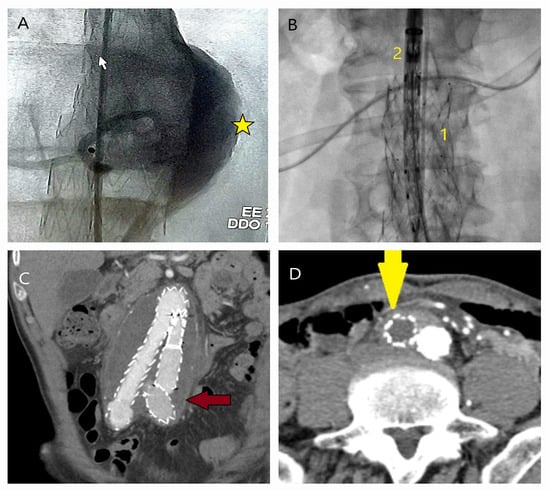

5.1. Failure of EVAR

5.2. Conversion to Open Surgery